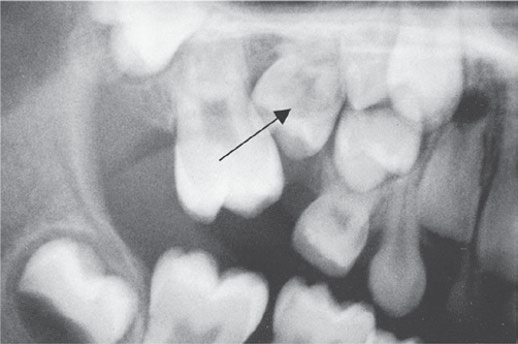

Hình 5.12: Răng hàm sữa thứ hai hàm trên bị ngầm (mũi tên) gây rối loạn mọc răng cho các răng cối nhỏ vĩnh viễn.

Răng sữa thường gặp nhất trong tình trạng này là răng hàm thứ hai hàm trên. Mầm răng bị lệch vị trí và chân răng thường cong, đi theo thành xoang hàm trong quá trình phát triển (Hình 5.12). Điều này có nghĩa là không thể kỳ vọng răng sẽ mọc tự nhiên. Răng ngầm này có thể gây nghiêng răng hàm lớn vĩnh viễn và làm rối loạn sự mọc của răng cối nhỏ vĩnh viễn. Răng sữa ngầm phải được loại bỏ bằng phẫu thuật.

Ngoài ra, răng hàm thứ hai sữa ở hàm dưới cũng có thể bị giữ lại, dẫn đến các vấn đề nghiêm trọng về mọc răng kế nhiệm vĩnh viễn.